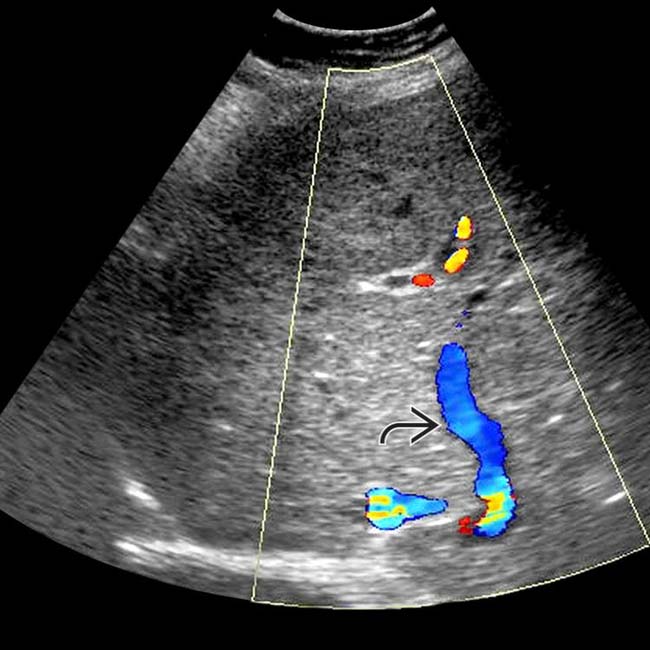

Doppler ultrasound of Budd Chiari syndrome & SOS Budd Chiari Syndrome Budd chiari syndrome is a rare disorder that causes narrowing and obstruction of the veins of the liver. Budd Chiari Syndrome.